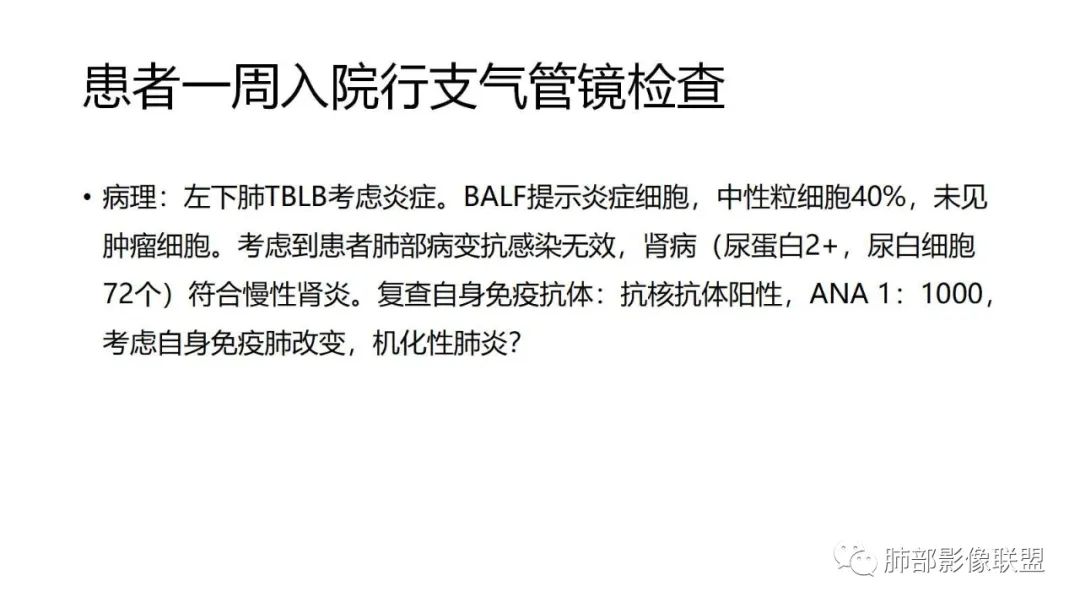

三、本例是一个误诊多年的病例,给我们很多启示:

1.多学科探讨的重要性:肾内科忽视肺部病变,后续需要呼吸、影像、病理共同探讨。

2.粘液腺癌易伪装成肺炎的形态,尤其是当患者本身具有免疫色彩的时候,易误诊为间质性肺炎,或肺部感染。若治疗无效,取得病理很重要。

3.粘液腺癌常常因为标本不够,病理无法诊断,影像诊断很重要,取病理方案很重要。甚至多次取病理。

4.回到本例,左下肺病变两次好转,均未经过肿瘤治疗,第一次是支气管镜后,第二次是当其他病变都在进展的情况下,左下肺病变范围反而缩小趋于浅淡。